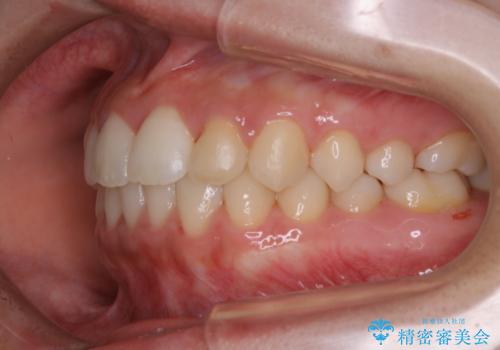

矯正治療終了後にPMTC(Professional Mechanical Tooth Cleaning)

- 矯正治療が終了したため、クリーニングでもきれいにしたいとのことでした。PMTC60分コースを行いました。

矯正治療が終わり、せっかくきれいになった歯並びも、虫歯・歯周病などになってしまっては元も子もありません。

矯正治療やセラミックなどによる被せ物の治療終了のタイミングではクリーニングを行い、汚れや着色の除去、歯と歯の間・歯と歯肉との境目などのケアをしっかりすることをおすすめしています。